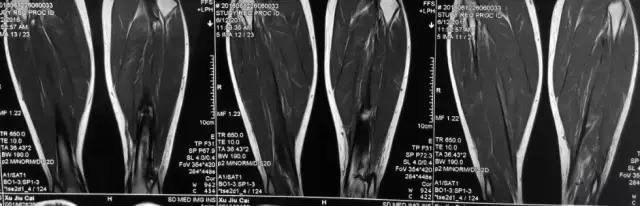

影像检查

诊断:感染。 检查:膝关节MRI,确认伤口窦道是否与髓腔相通。 治疗:1、血沉和C反应蛋白正常,目前无需特殊处理。 2、如果窦道反复出现或血沉和C反应蛋白升高可考虑手术。如证明窦道与髓腔相通,需行扩髓。

核磁示中下段骨髓炎,上面切口处流脓,请问张主任你的意见要上手术吗?